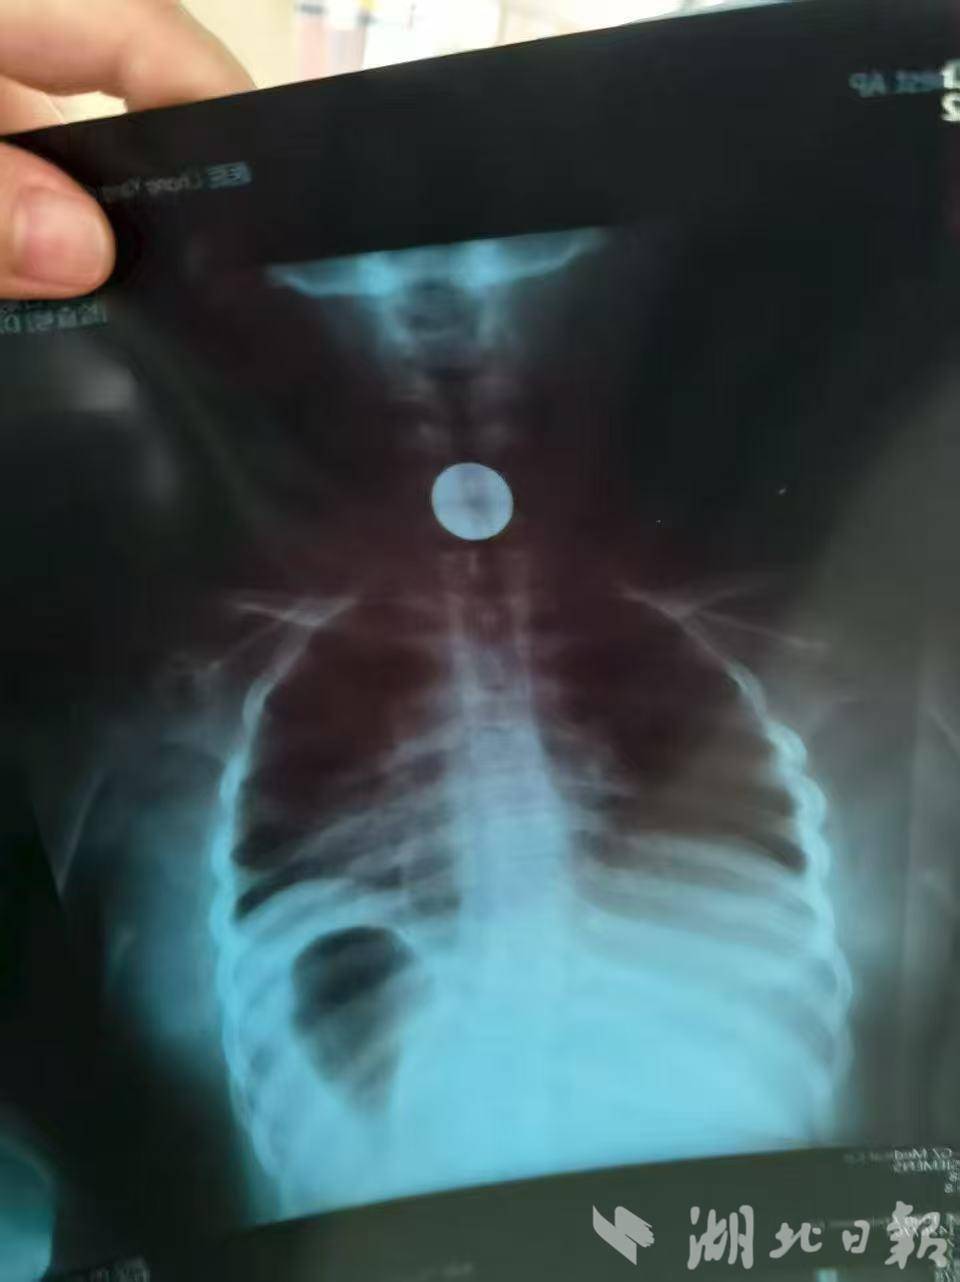

» 吞 下 一元 硬币 (99) 사진

吞 下 一元 硬币 (99) 사진

一元 硬币